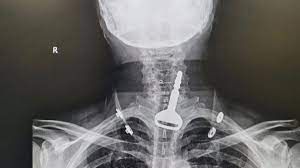

وأوضحت صحة مدينة القنفذة أن المريض، البالغ من العمر 49 عاماً، وصل لقسم الطوارئ وهو يعاني من انسداد بمجرى التنفس، ليتضح بعد الفحص السريري والأشعة وجود مفتاح سيارة عالق في القصبة الهوائية.واعترف المريض للأطباء المعالجين بأنه ابتلع المفتاح أثناء لهوه به، ما تسبب له في حالة اختناق جزئي تطلب التدخل الجراحي عن طريق المنظار لاستخراج الجسم المعدني العالق.

وتقرر فورًا إدخال المريض قسم العمليات وتكثيف العناية الصحية له لكونه مريض قلب، وتم إجراء التدخل الجراحي عن طريق المنظار واستخراج المفتاح، ومن ثم متابعة الحالة عن طريق قسم التنويم لحين استقرار حالته الصحية وخروجه بالسلامة.